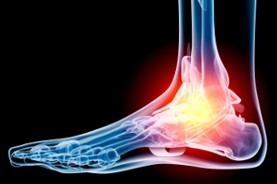

Shockwave Therapy

We offer the new, advanced technology known as Extracorporeal Radial Shock Wave Therapy (ESWT) or (RSWT). This technology reduces or eliminates many types of chronic pain. Radial Shockwave Therapy is fast, safe, non-invasive and very effective in treating many problems for which, traditionally, patients were unable to receive effective medical treatment.

At the Alberta Foot Institute, our Doctors are trained to specifically treat problems associated with your feet or ankles. Below are several of the most common problems that we see on a day to day basis: